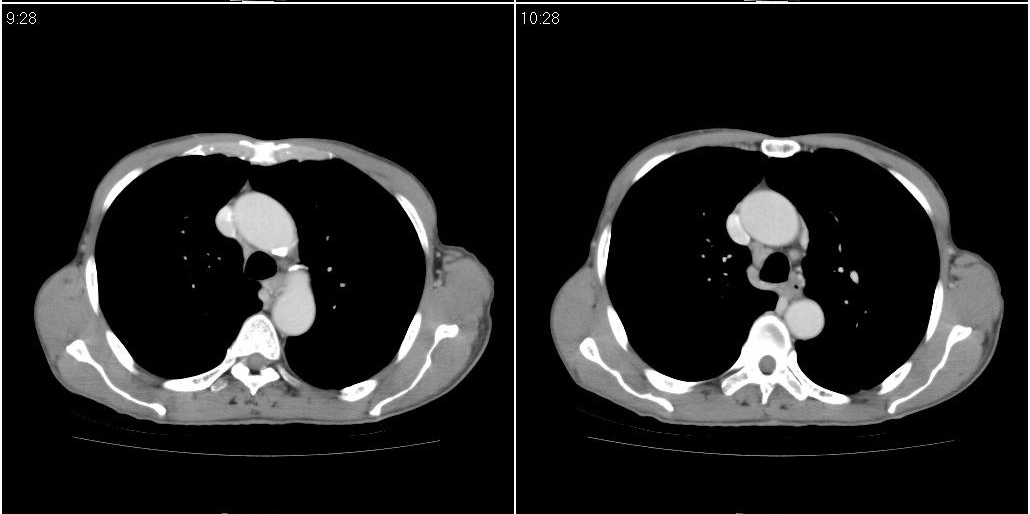

标题: CT25416:男性,70岁。胸片发现右下肺斑片状阴影

以下是ct检查的情况:

标题: ct增强: